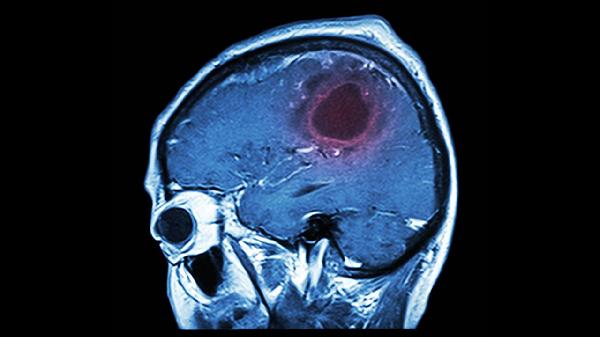

脑溢血手术后有什么后遗症

脑溢血手术后可能出现运动功能障碍、语言障碍、认知功能下降、癫痫发作、情绪障碍等后遗症。脑溢血手术后的后遗症与出血部位、出血量、手术时机等因素有关,患者需在医生指导下进行康复训练和药物治疗。